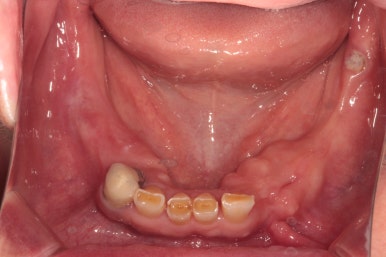

전체적으로 어금니가 여러개 없어요. 앞니는 깨졌어요.

처음 오셨을 때 촬영한 정면 구강 내 사진입니다.

위 앞니 보철물은 도재 (포세린,porcelain)가 깨져있어 보기 흉한 상태였고, 대부분의 어금니가 없으신 상황..

지금까지 어떻게 식사하셨을까요 ㅠㅠ

양옆으로 보았을 때도 아래 어금니는 모두 없어진 상태이고, 쓸수 있는 치아가 많지 않았어요.

입천장쪽에서 바라 보았을 때 왼쪽 위 어금니는 뿌리만 남아 발치하였습니다.

아래턱은 보시다시피 치아가 5개 밖에 남지 않았어요.